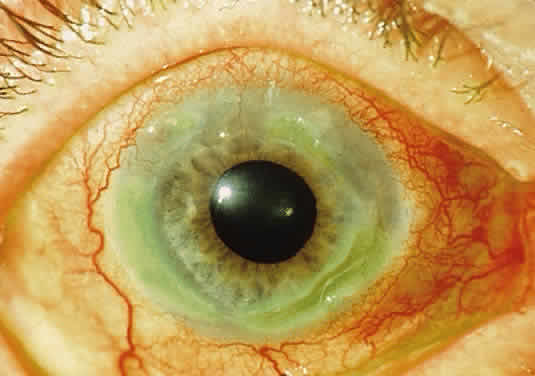

OCULAR FINDINGS. One of the few truly diagnostic and pathognomonic physical signs in clinical medicine is a Kayser-Fleischer corneal pigment ring found in patients with Wilson's disease (Fig. 5).This ring is recognized as a golden-brown, ruby-red, or green band of 1.0 to 3.0 mm, starting at the limbus but at the level of Descemet's membrane.53 The color of the ring is presumably caused by scattering and reflection of incident light and by photointerference effects created by the layers of copper granules. Such variables as size, shape, and unit density of the granules may account for the different appearances of the Kayser-Fleischer ring. The course of the Kayser-Fleischer ring has been well documented.54,55 The site of earliest pigment deposition is an arc in the superior periphery of the cornea from the 10- to 2-o'clock meridian. The arc spreads slowly toward the horizontal plane and gradually broadens. Later in the progression of the ring formation, a band appears inferiorly as a crescent stretching from the 5- to 7-o'clock positions. In time, the two arcs meet. With treatment, the sequence of events is reversed, and after the copper has reabsorbed, a pitted or beaten silver pattern may become apparent at the previous site of the ring. This is an indication that treatment has produced a negative copper balance.49 Decreased visual acuity is not a problem. Rarely, copper is deposited in the crystalline lens, giving an anterior subcapsular “sunflower” cataract.